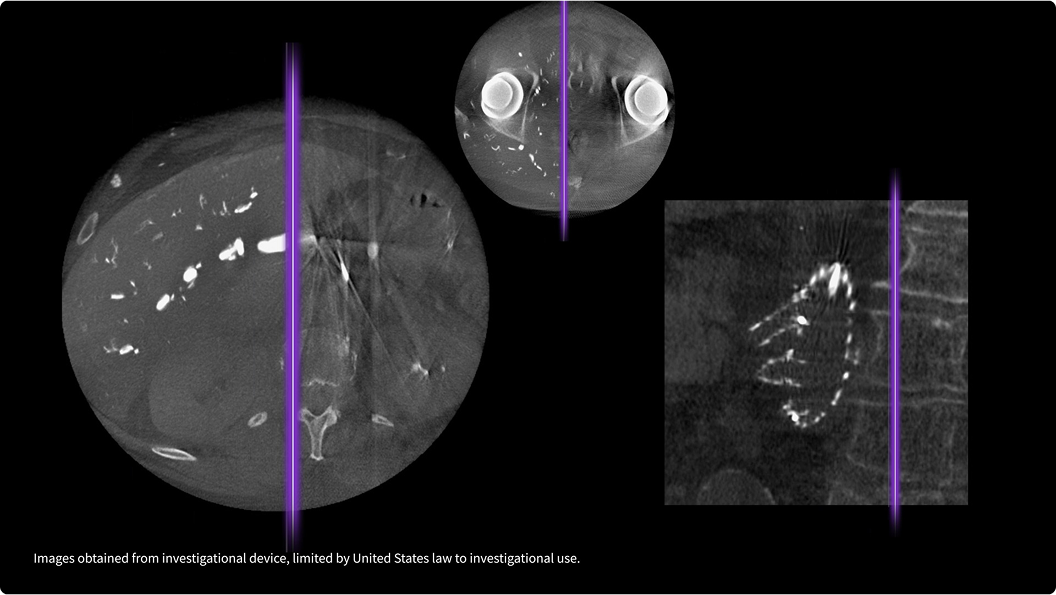

Visualisez une interface os-implant métallique nette, sans artefact de halo.

Détail anatomique exceptionnel à faible dose

Le traitement d’image avancé Helix offre une netteté inégalée, un contraste équilibré et une luminosité optimale, même face aux variations de dose, à l’anatomie du patient et à la présence d’implants métalliques complexes. Disponible sur l’ensemble de nos systèmes de radiographie fixes et mobiles, Helix garantit des performances constantes, quel que soit le protocole d’exposition ou les conditions d’examen.